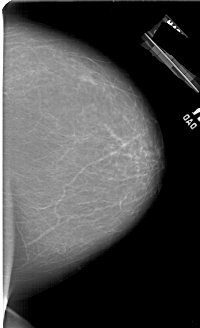

A_1450_1.RIGHT_MLO

RIGHT_MLO LINES 6871 PIXELS_PER_LINE 4471 BITS_PER_PIXEL 12 RESOLUTION 43.5 NON_OVERLAY